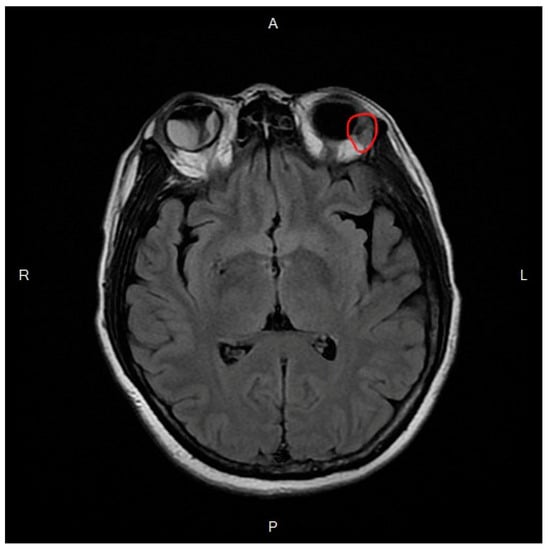

Adjuvant Intravitreal Bevacizumab Injection for Choroidal and Orbital Metastases of Refractory Invasive Ductal Carcinoma of the Breast

2. Case Report